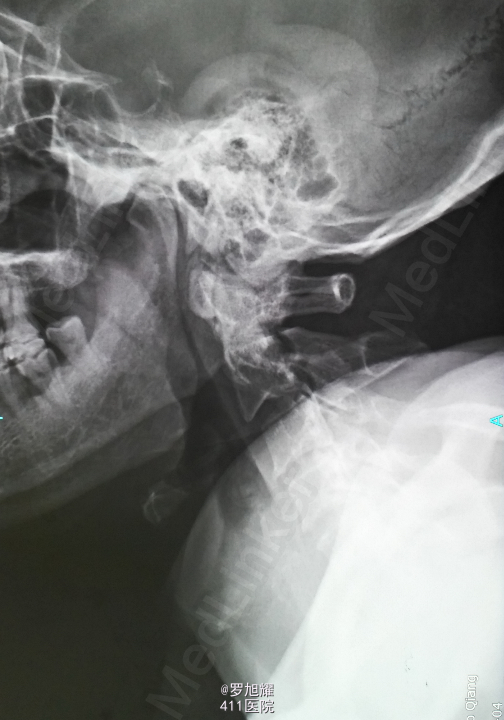

患者男性,64岁。因车祸致颈部疼痛、四肢麻木乏力2小时入院。 该患者同时还有头皮血肿、轻型闭合性颅脑损伤,后期再确诊右肩袖损伤。

左侧锁骨平面以下痛温觉、位置觉消失,右半身感觉正常。会阴部感觉存在。左侧肢体肌力正常,右侧上下肢肌力0级。右侧腱反射均消失。影像学检查示双侧枢椎椎弓骨折,MRI脂肪抑制成像颈1-2平面脊髓信号略高。